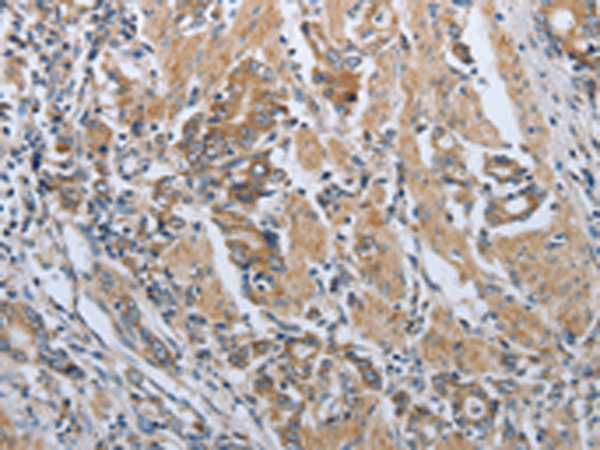

分类: 科研抗体货号: P04420别名: PRKAR1应用: WB,IHC反应种属: Human, Mouse, Rat